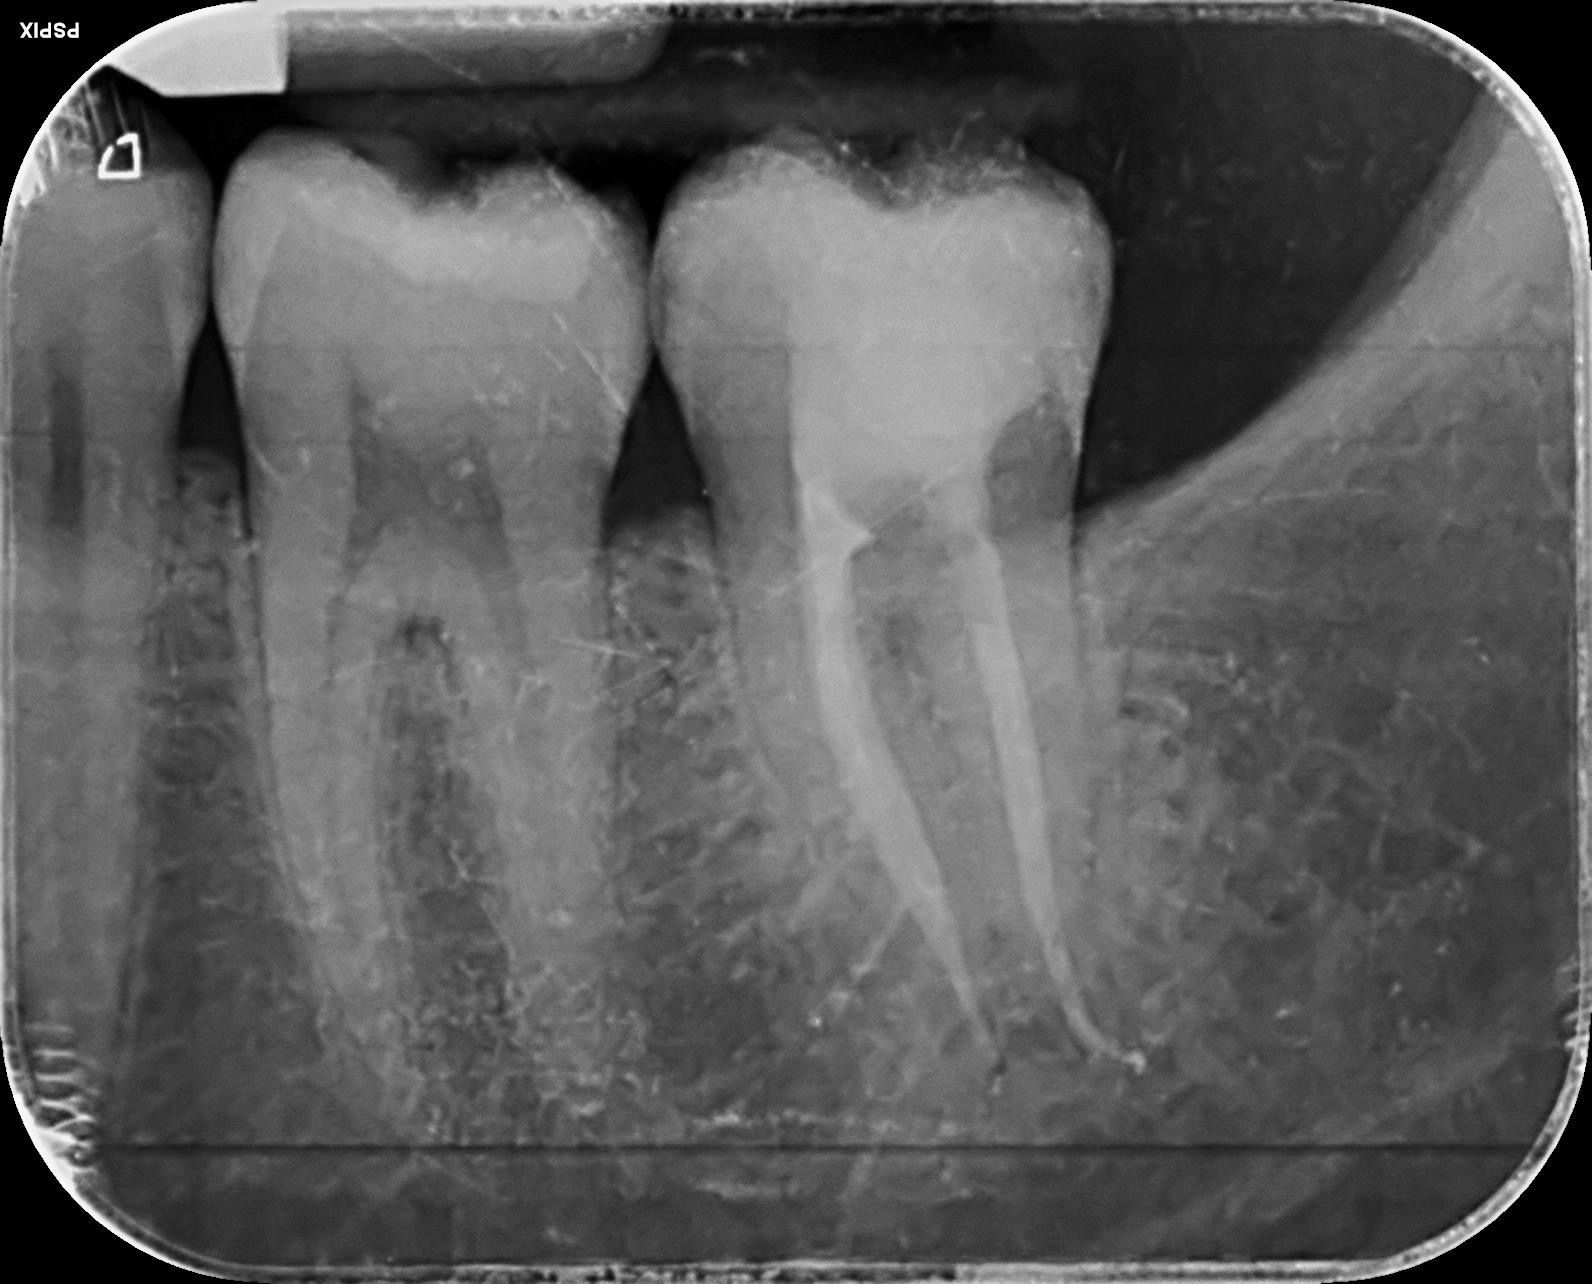

Caso 2